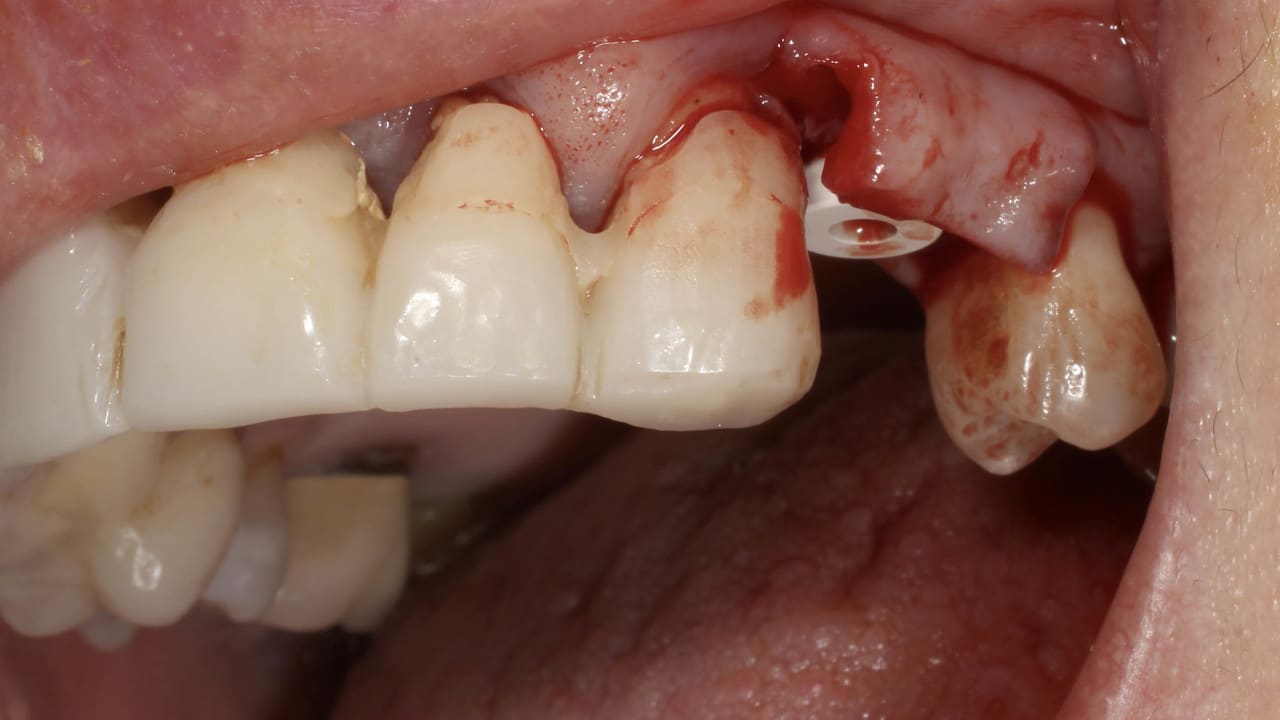

La « Strip Technique » : une solution de vestibuloplastie simple et reproductible

La technique de la bandelette ou « Strip Technique » permet de réduire les suites liées à ce type de prélèvement en garantissant une cicatrisation plus rapide du site donneur.

Lors de réhabilitations complexes incluant des reconstructions osseuses pré-implantaires de grande étendue, la perte de tissu kératinisé et le déplacement coronaire de la ligne muco-gingivale (LMG) constituent un défi dans la gestion des tissus mous. Bien souvent, si on a bien travaillé, on se retrouve avec un volume osseux restauré. La radio est hyper séduisante et le volume à implanter tout à fait généreux. Mais cliniquement, que dire de la gencive, du vestibule ? Quel site donneur pour une grande étendue ? Et pas question dans ce cas de se contenter d'un greffon conjonctif enfoui ; pas le choix dans ce cas !

Les solutions devront s'équilibrer entre l'étendue des sites donneurs (le palais la plupart du temps) et l'usage de matrices d'origine xénogéniques ou allogéniques.<